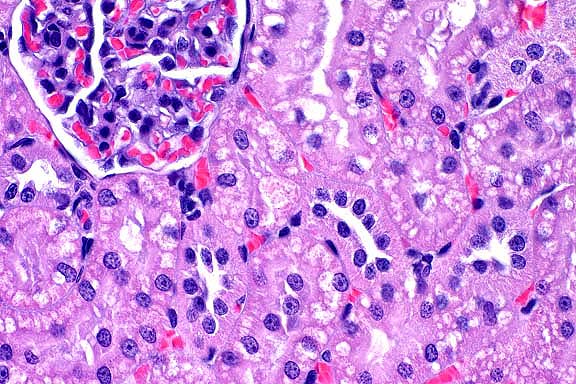

obj

- Case 12-3. Ocular tumor. Sheets of pleomorphic polygonal

cells occasionally palisade around a central lumen (pseudorosette

formation).

- Conference Note: This neoplasm was studied in consultation

with the Department of Ophthalmic Pathology. Conference participants

agreed with the contributor's diagnosis. An expansile, infiltrative,

densely cellular neoplasm has effaced the ciliary body and is

composed of polygonal cells arranged in packets, nests, tubular

structures, and pseudorosettes, supported by a fine fibrovascular

stroma. Neoplastic cells have significant atypia, with occasional

bizarre cells. The mitotic rate is high. Scattered within the

tumor are entrapped melanophages which contain moderate amounts

of brown-black granular to globular pigment.

- Immunohistochemical studies performed at the AFIP demonstrate

that the tumor is multifocally positive for both keratin and

vimentin, and negative for S-100 protein. The PAS reaction demonstrates

that neoplastic cells align along a PAS-positive basement membrane,

supporting the diagnosis of ciliary body adenocarcinoma.